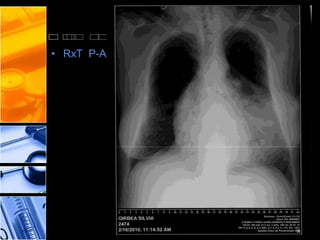

• RxT P-A

Ziua 5 p.o.: RxT – imagine hidroaerica cu nivel

orizontal de lichid localizata in mediastinul anterior,

pana in etajul mijlociu; desen pulmonar normal.

RxT – reducerea imaginii hidro-aerice din mediastinul

anterior, fata de examinarea precedenta.

- desen pulmonar normal.